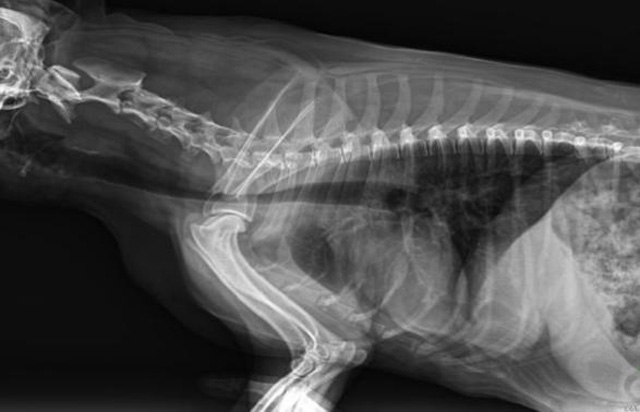

從臨床角度出發(fā),大力發(fā)展動態(tài)DR,以精準(zhǔn)的診斷為小動物保駕護(hù)航。寵物DR升級使用雙焦點球管,大尺寸平板探測器,超高頻逆變高壓發(fā)生器。醫(yī)用纖維板臺面,防止寵物劃傷。寵物DR整機小巧實用,骨略結(jié)構(gòu)和器官位置,分類詳細(xì),運算更快,讓拍攝條件更科學(xué),有助于提高診斷的準(zhǔn)確性和效率。安裝移動非常方便。低輸入電流設(shè)計,220伏常規(guī)電壓。多品種動物程序設(shè)定,滿足各個臨床需求。成像效果顯著,寵物不能言語表達(dá),導(dǎo)致誤診率居高不下。寵物診療均以經(jīng)驗診斷為主的方式,確保最小化輻射降低對醫(yī)生及動物的影響。以滿足精細(xì)化的寵物醫(yī)療需求,成為診斷寵物內(nèi)外科疾病的必備工具。使醫(yī)院更有競爭力,為醫(yī)院創(chuàng)收增光添彩。

寵物DR的操作流程是什么呢?第一步首先插上整機電源,然后按下主機電源。打開高壓發(fā)生器的電源,工作站主機電源。等待主機軟件的自動啟動。通過軟件登記檢查的寵物信息,選擇寵物檢查拍攝部位。調(diào)節(jié)限速器拍攝區(qū)域。關(guān)閉鉛房門,點擊開始拍攝按鈕。拍攝完成調(diào)整圖像并且輸出。